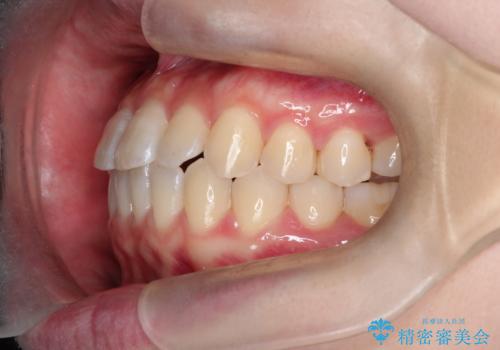

前歯と奥歯のガタガタを矯正で改善

- 患者様は、前歯と奥歯のガタガタ(叢生)を改善し、正面から見た時の歯並びを美しく整えたいとのご要望で来院されました。診断の結果、非抜歯での矯正が可能と判断し、インビザラインを使用する治療計画を立案しました。透明な矯正装置で目立ちにくい治療を行いながら、前歯と奥歯の両方を整列させることを目標にしました。

インビザラインを用いて、前歯の見た目を重視しつつ、奥歯のガタガタも改善しました。特に正面から見た際の美しい歯列を意識し、段階的に歯を移動させることで、全体の調和を図りました。治療中は、適切な装着時間を守ることや、装置の清潔を保つことが重要でした。また、歯肉や歯列全体に無理な負担がかからないように移動を管理しながら治療を進めました。結果として、前歯と奥歯がきれいに並び、見た目にも機能的にも満足いただける仕上がりとなりました。